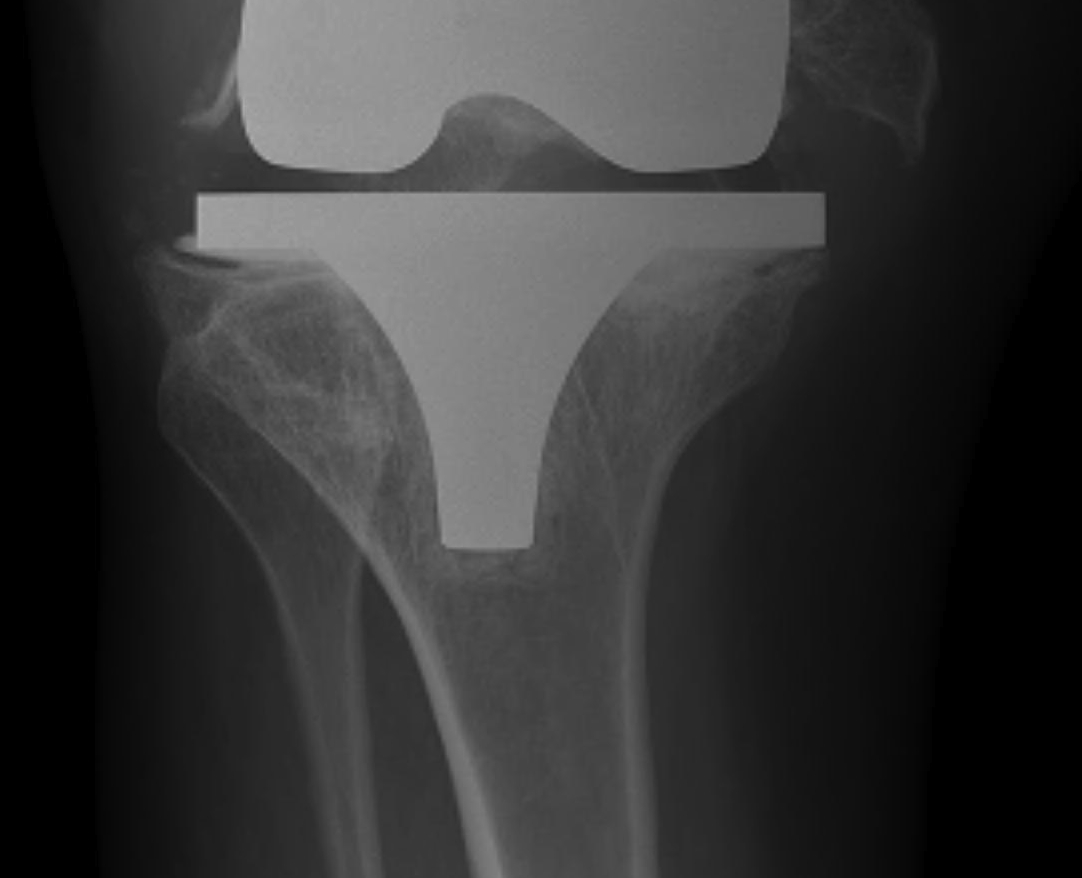

Most systems use Classic Alignment & Matched Resection

- cut tibia and femur perpendicular to MA

- ER femur 3°

- balance soft tissues